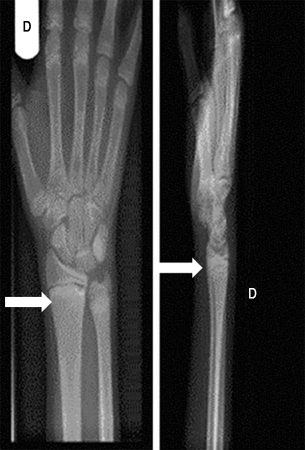

Uma radiografia de um osso longo revelando escavação, afunilamento e desgaste da metáfise é necessária para o diagnóstico. O alargamento da placa epifisária e a perda de definição da zona de calcificação provisória na interface epífise/metáfise são os primeiros sinais de raquitismo.

A ulna distal é o local que melhor demonstra os sinais precoces da mineralização prejudicada, e as metáfises acima e abaixo dos joelhos são os locais mais úteis em crianças mais velhas.[4][Figure caption and citation for the preceding image starts]: Punho direito de um paciente com raquitismo por deficiência de vitamina D antes do tratamento. Sua radiografia do punho direito revelou placas finais escleróticas e aumentadas do rádio e ulna (setas)Seerat I, Greenberg M. Hypocalcaemic fit in an adolescent boy with undiagnosed rickets. BMJ Case Reports 2010; doi:10.1136/bcr.10.1136/bcr10.2008.1153 [Citation ends].

[Figure caption and citation for the preceding image starts]: Punho direito de um paciente com raquitismo por deficiência de vitamina D depois do tratamento (setas)Seerat I, Greenberg M. Hypocalcaemic fit in an adolescent boy with undiagnosed rickets. BMJ Case Reports 2010; doi:10.1136/bcr.10.1136/bcr10.2008.1153 [Citation ends].